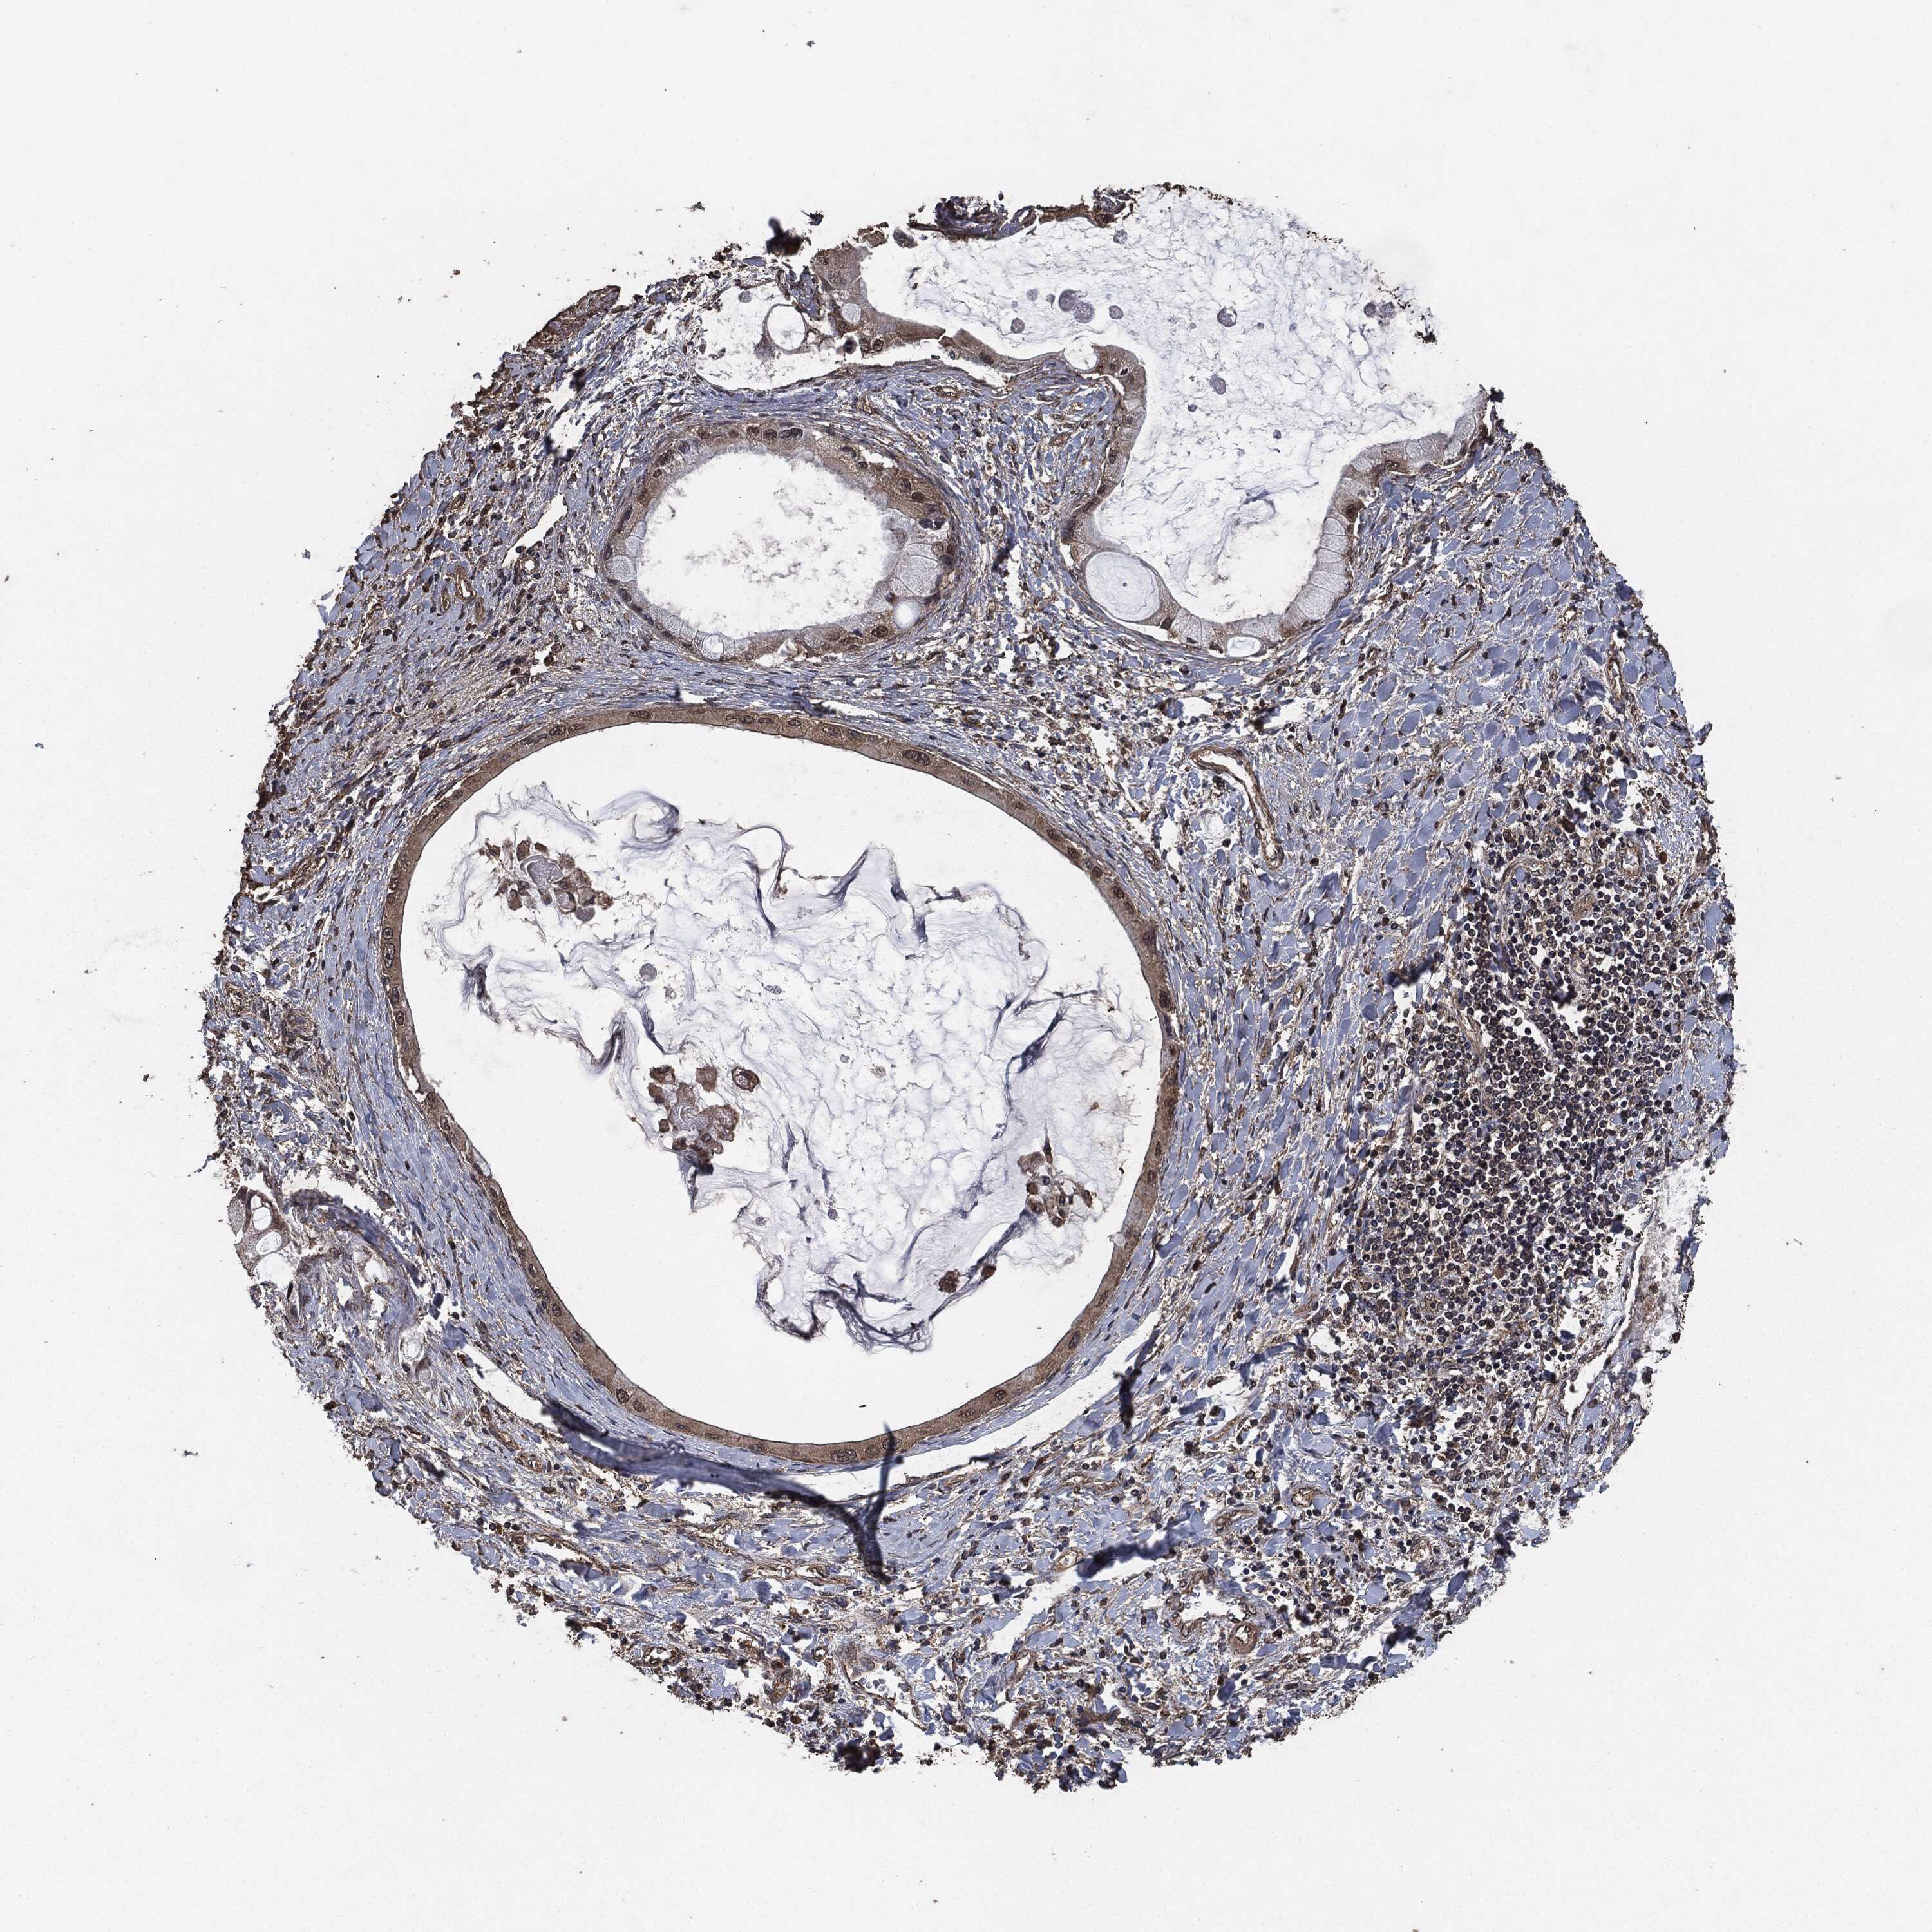

LIVER CANCER - Protein expressioni

A mouse-over function shows sample information and annotation data. Click on an image to view it in a full screen mode. Samples can be filtered based on level of antibody staining by selecting one or several of the following categories: high, medium, low and not detected. The assay and annotation is described here.

Note that samples used for immunohistochemistry by the Human Protein Atlas do not correspond to samples in the TCGA dataset.

Antibody stainingi

Antibody staining in the annotated cell types in the current human tissue is reported as not detected, low, medium, or high, based on conventional immunohistochemistry profiling in selected tissues. This score is based on the combination of the staining intensity and fraction of stained cells.

Each image is clickable and will lead to virtual microscopy that enables deeper exploration of all samples and also displays staining intensity scores, fraction scores and subcellular localization as well as patient and tissue information for each sample.

Antibody HPA064427

Antibody HPA075510

Antibody CAB021903

Staining

High

Medium

Low

Not detected

Intensity

Strong

Moderate

Weak

Negative

Quantity

>75%

75%-25%

<25%

None

Location

Nuclear

Cytoplasmic/membranous

Cytoplasmic/membranous,nuclear

Carcinoma, Hepatocellular, NOS

Cholangiocarcinoma